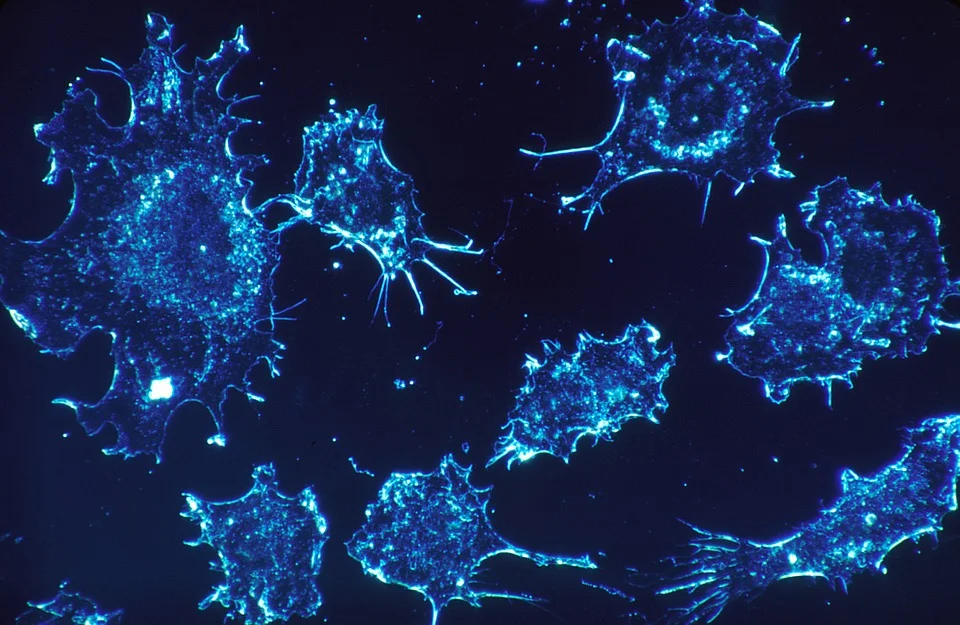

4. Fights and Protects Against Cancer

Milk Thistle is most well known for its antioxidant and chemoprotective effects on the liver. R R R R R R R

Silymarin has been shown to inhibit various systems such as leukotriene synthesis, the effects of TNFα. R

In children with ALL (acute lymphoblastic leukemia), milk thistle is correlated to to reduction in liver toxicity. R

In combination with selenium, milk thistle reduced LDL and total cholesterol in men after prostrate removal from prostate cancer, which are associated with prostate cancer progression. R

In combination with omega-3 fatty acids, brain metastases patients had longer survival times and decreased percentage of tissue death from radiotherapy. R

Topical treatment of silymarin inhibited several tumor promoters and may be useful in sun protection. R

The protective effects of silymarin suggest a clinical application in cancer patients as an adjunct to established therapies, to prevent or reduce chemotherapy as well as radiotherapy-induced toxicity. R

In patients with breast cancer, milk thistle (cream) may be an effective treatment for preventing skin lesions form radiotherapy. R

In human cancer cells, it inhibited the proliferation and promoted cell cycle arrest of the cells. R R

It inhibited osteosarcoma cells. R

It induced autophagy in kidney cancer. R

It induced destruction of laryngeal cancer cells. R

Isosilybin B may help with prostate cancer prevention and treatment by destroying prostate cancer cells. R R

In animals:

- Milk-thistle compounds painted on the skin of mice exposed to ultraviolet radiation prevented the development of skin cancers. R

- It inhibited prostate tumor growth, progression, invasion and spread. R R

- It delayed the development of spontaneous breast tumors and tumor mass. R R

- It prevented N-butyl-N-(4-hydroxybutyl)nitrosamine (OH-BBN)-induced bladder cancer. R

Although promising, there needs to be more clinical trials on milk thistle for cancer treatment .

In cancer:

- Milk thistle induces growth arrest at g1 and g2 checkpoints. R

- It leads to apoptosis through MAPK (mitogen activated protein kinase) / JNK (c-Jun-N-terminal kinase) pathway. R

- It decreases PSA prostate specific antigen) expression. R

- It controls the expression of Caspace-3 and PARP (Poly ADP ribose polymerase). R

- It inhibits EGFR (Epidermal Growth Factor Receptor) signaling. R

- It supresses CDK (cyclin dependent kinase) expression. R

- It increases CDK-inhibitors p21(C1P1) and p27 (K1P1). R

- It inhibits ERK1/2 (extracellular signal regulated kinases). R

- It inhibits TGF-α. R

- It decreases cyclin B1 and cdc2. R

- It increases p21 expression. R

- It activates SIRT1 pathway. R